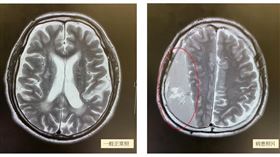

驚!半邊身體無力竟是「硬腦膜下出血」

跌倒撞到頭的經驗大家都有,我們有時候會以為,頭部只是...